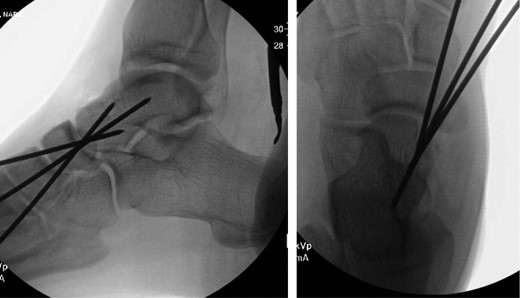

Once general anesthesia was induced, closed reduction was attempted using axial traction with the knee in flexion. Closed reduction was unsuccessful once again (Fig. 3) so the decision was made to attempt open reduction. An anteromedial approach was used dissect down to the talonavicular joint. Retractors were placed with care to avoid injury to tibialis anterior tendon or superficial peroneal nerve. The joint capsule was seen to be disrupted and further exposure revealed a thin, coronal fracture of the anteromedial aspect of the talar head measuring roughly 2 cm in length and 6 mm in thickness (Fig. 4). Once this fragment was removed, the subtalar and talonavicular joints were easily reduced. It was thought that this incarcerated fragment was the likely cause for the unsuccessful closed reduction. The talar head fragment was unamendable for stabilization due to its small size with poor healing potential, thus it was removed. The talonavicular joint was then percutaneously pinned in retrograde fashion with three K-wires (Fig. 5) to maintain anatomic reduction of the subtalar and talonavicular joints and the foot was splinted. At 2 weeks follow-up the patient was doing well and radiographs revealed no interval loss of reduction (Fig. 6).

Some studies suggest obtaining a CT scan of the ankle postreduction to check anatomic reduction as well as assess for other fractures [8, 9]. In our case, we did not obtain a postreduction CT scan. The subtalar and talonavicular joint were well visualized intraoperatively and were found to have no other associated fractures. In addition, anatomic reduction was obtained and under direct visualization and confirmed with fluoroscopy. Due to residual instability following reduction, K-wires were used to stabilize and hold the reduction. K-wire transfixation is supported in the literature for subtalar dislocations which tend to redislocate [10]. In other cases, where the joint is stable after reduction, there is no need for fixation.

In the case report presented, a medially displaced subtalar dislocation was found to be irreducible using closed techniques. During open reduction, an anteromedial talar head fracture fragment was found be blocking the reduction. Once removed, the dislocation was easily reduced, but still unstable. Three K-wires retrograde percutaneous K-wires were placed across the talonavicular joint to hold the reduction. Short-term follow-up has been unremarkable.